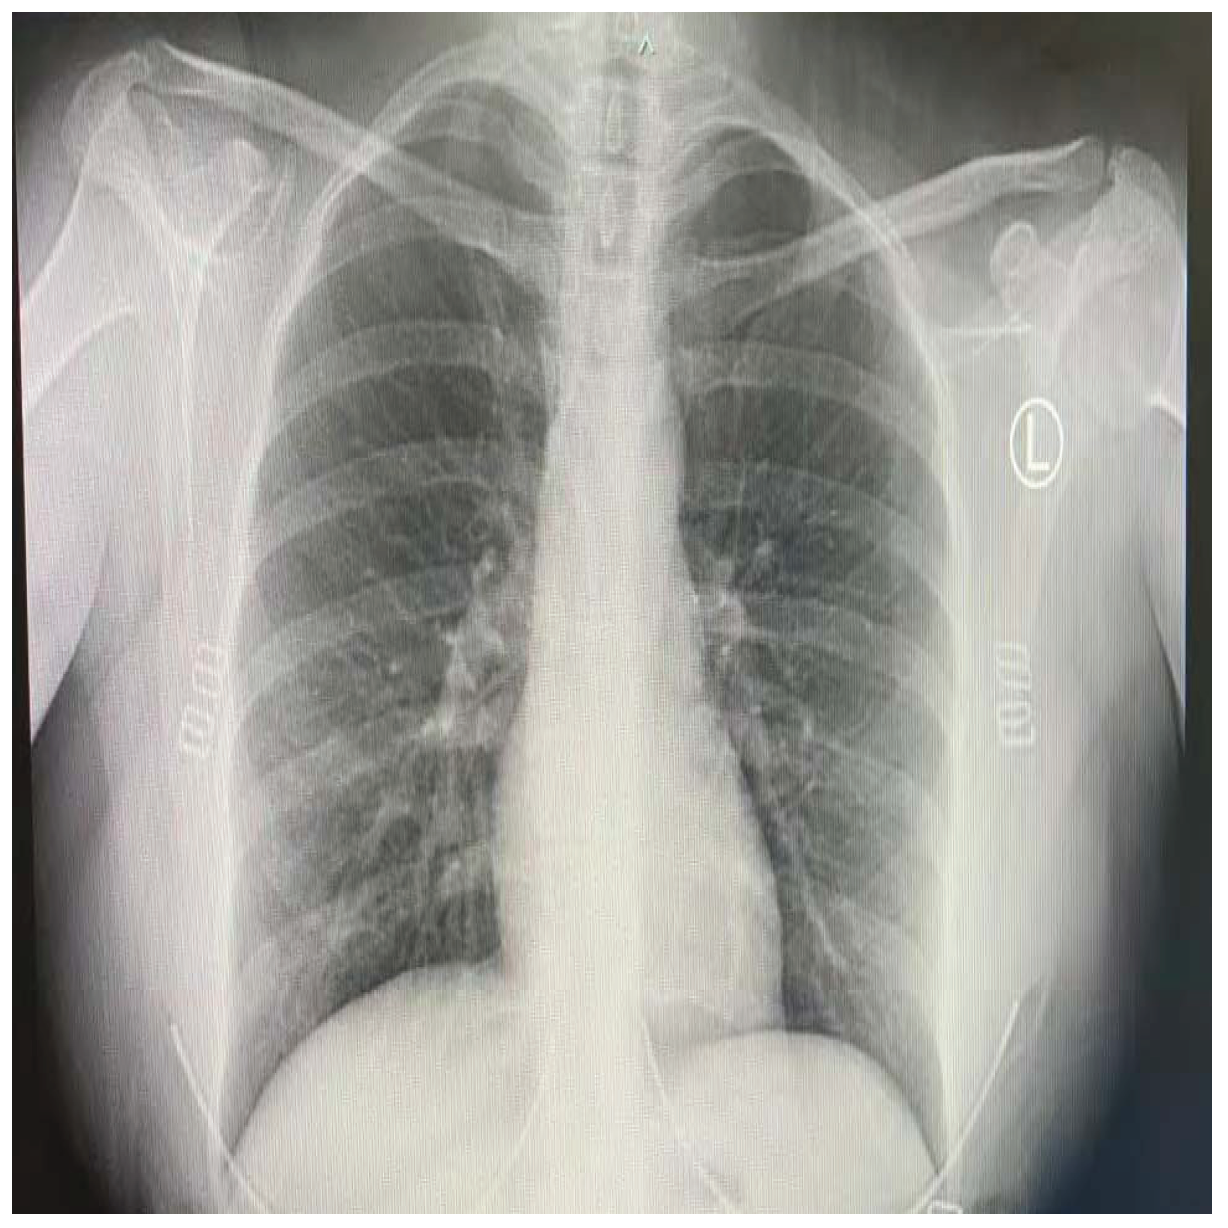

COVID-19 patients who have clinical symptoms are more likely to show abnormal CXR [9]. The main findings of recent studies suggest that these lung images display patchy or diffuse reticular–nodular opacities and consolidation, with basal, peripheral, and bilateral predominance [10]. For example, Figure 1 shows the CXR of a mild case of lung tissue involvement with right infrahilar reticular–nodular opacity. Moreover, Figure 2 shows the CXR of a moderate to severe case of lung tissue involvement. This CXR shows right lower zone lung consolidation and diffuse bilateral airspace reticular–nodular opacities, which are more prominent on peripheral parts of lower zones. Similarly, Figure 3 shows the CXR of a severe case of lung tissue involvement. This is caused by diffuse bilateral airspace reticular–nodular opacities that are more prominent on peripheral parts of the lower zones, and ground glass opacity in both lungs predominant in mid-zones and lower zones. On the other hand, Figure 4 shows an unremarkable CXR with clear lungs and acute costophrenic angles (i.e., normal).

Figure 1.

CXR of COVID-19 subject showing mild lung tissue involvement.